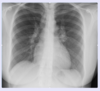

What is the likely diagnosis in a young woman with shortness of breath and the CXR findings below?

Sarcoidosis